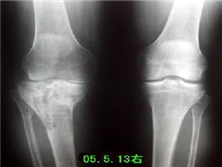

髌骨软骨软化症

髌骨软骨软化症是髌骨软骨表面因慢性损伤而肿胀、开裂、破碎、侵蚀、脱落的骨关节病。...